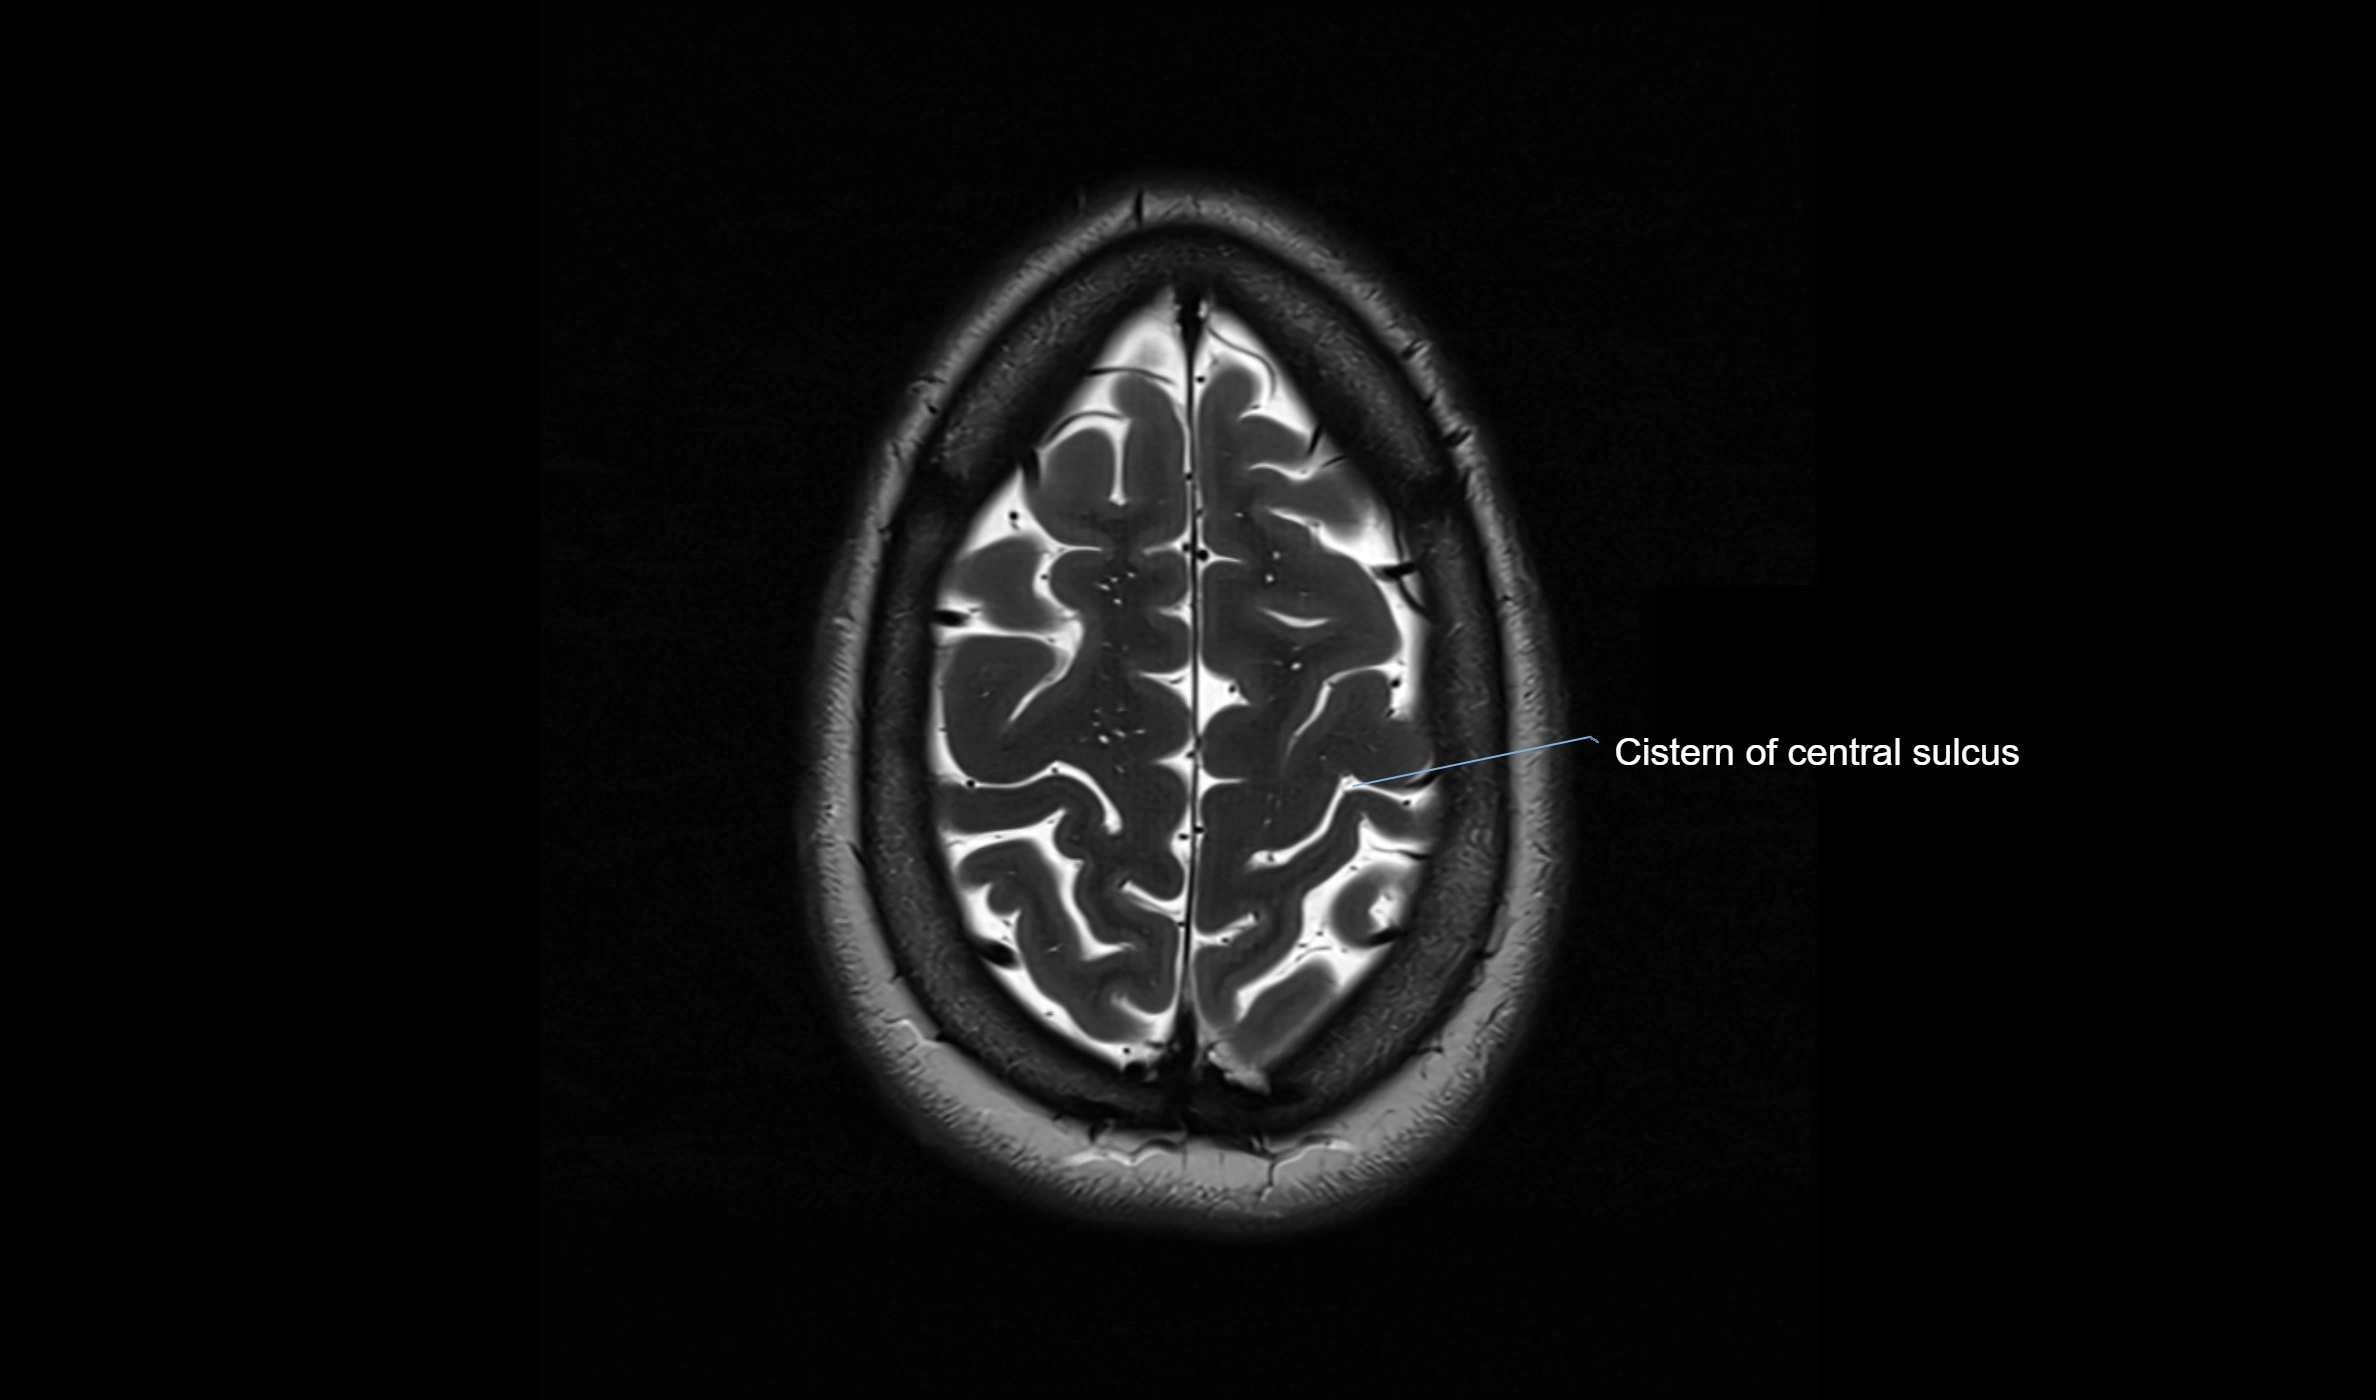

MRI images

image